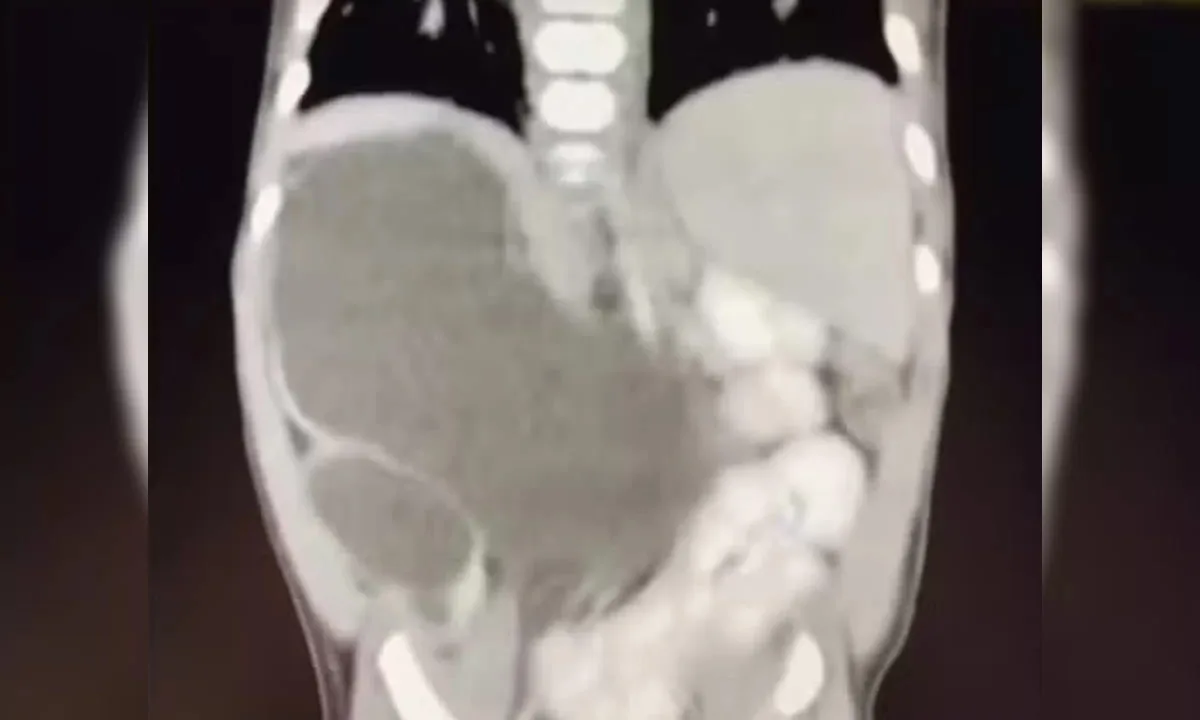

Incluída nos casos raríssimos da medicina, uma menina nasceu com quatro rins. Hoje com 1 ano e 1 mês, a pequena Isis Eloah Ferreira Alves está entre os cerca de 100 casos da medicina documentados na literatura mundial. O caso, publicado pelo G1, é é conhecido na medicina como “rins supranumerários” e demanda acompanhamento.

Aos 5 meses, quando houve a necessidade de Isis passar por uma cirurgia, os médicos confirmaram que ela tinha nascido com quatro rins. Como Formosa fica a cerca de 80 quilômetros do Distrito Federal, a menina hoje é tratada no Hospital da Criança de Brasília (HCB).